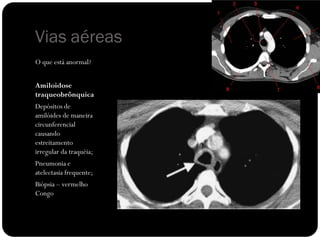

O que está anormal?

Vias aéreas

Amiloidose

traqueobrônquica

Depósitos de

amilóides de maneira

circunferencial

causando

estreitamento

irregular da traquéia;

Pneumonia e

atelectasia frequente;

Biópsia – vermelho

Congo